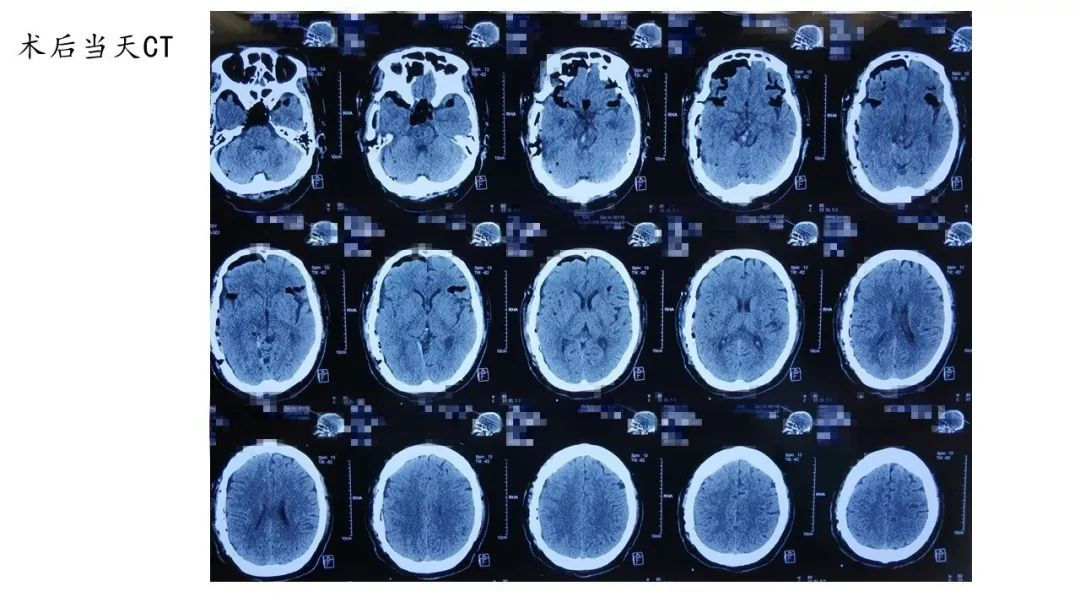

一周后,行右侧颈内动脉内膜剥脱术,术中使用FT960T做临时阻断。

复查CTA如下图:

术后复查CTA右侧颈内动脉起始部狭窄和左侧颈内动脉岩骨段狭窄均有明显改善。